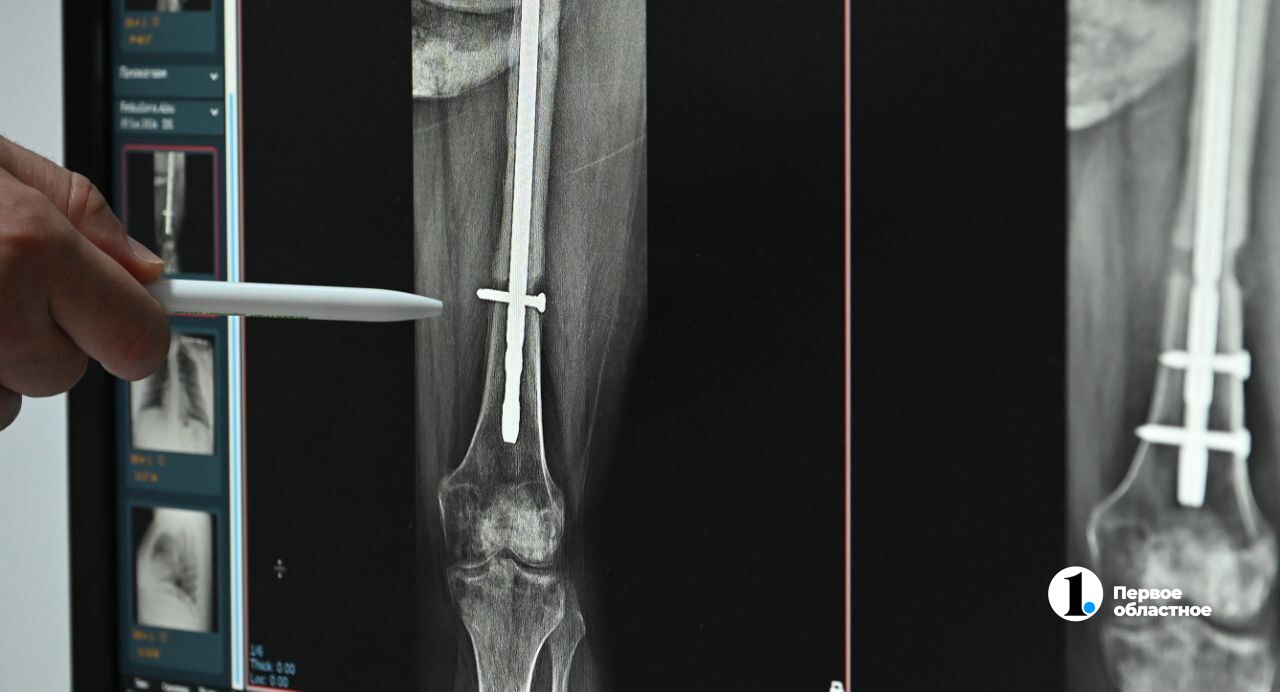

Два года назад машина, в которой с другом ехала Алсу Феткулова, врезалась в столб напротив цинкового завода. В больнице женщине ампутировали одну ногу, а переломанные кости второй ноги укрепили штырями. Медики ждали, что кости срастутся, нога окрепнет и Алсу сможет ходить на протезе.

Однако кости второй ноги не срастались — на эту ногу нельзя было опереться. К тому же женщину мучили постоянные боли. И Алсу обратилась за помощью в другую клинику, к другим врачам.

Травматологи удалили прежний фиксатор, выполнили костную пластику, а на место старого установили новый фиксатор.